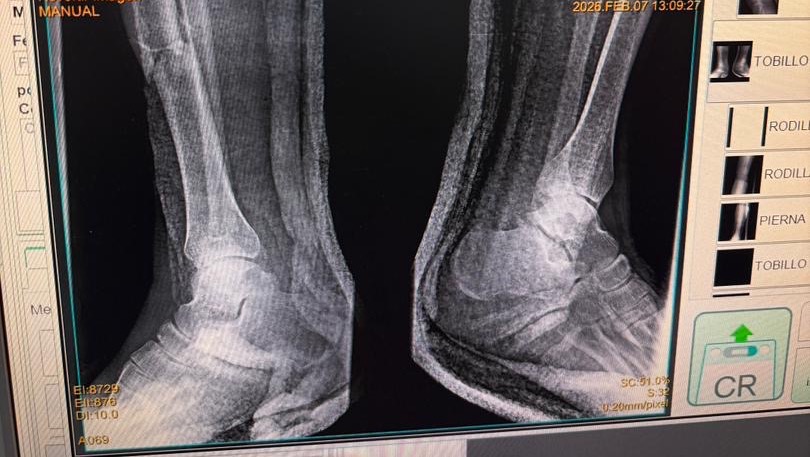

A sus 27 años, Jean Manuel Colella estaba cumpliendo una de sus metas más grandes: realizar sus prácticas universitarias en Barquisimeto, Venezuela. Sin embargo, la madrugada del 07 de febrero, su vida cambió en un segundo. Fue víctima de un terrible accidente automovilístico donde, lamentablemente, los responsables se dieron a la fuga, dejándolo atrás con heridas graves. Hoy, Jean Manuel enfrenta el reto más difícil de su vida. El accidente le causó múltiples fracturas en ambas piernas, siendo su pie derecho el más afectado. Para que él pueda volver a caminar, trabajar y terminar su carrera, necesita una cirugía de reconstrucción urgente. Cada granito de arena cuenta. Tu donación, por pequeña que parezca, es un paso más cerca de devolverle la movilidad a un joven que tiene todo un futuro por delante. ¡Ayúdanos a que Jean Manuel vuelva a ponerse de pie!

At the age of 27, Jean Manuel Colella was achieving one of his biggest goals: completing his university internship in Barquisimeto, Venezuela. However, in the early hours of February 7th, his life changed in an instant. He was the victim of a horrific car accident where, heartlessly, those responsible fled the scene, leaving him behind with severe injuries. Today, Jean Manuel faces the toughest challenge of his life. The accident caused multiple fractures in both legs, with his right foot being the most severely affected. In order for him to walk again, work, and finish his degree, he needs urgent reconstructive surgery. Every little bit helps. Your donation, no matter how small it may seem, is one step closer to restoring mobility to a young man with his whole future ahead of him. Help us get Jean Manuel back on his feet!